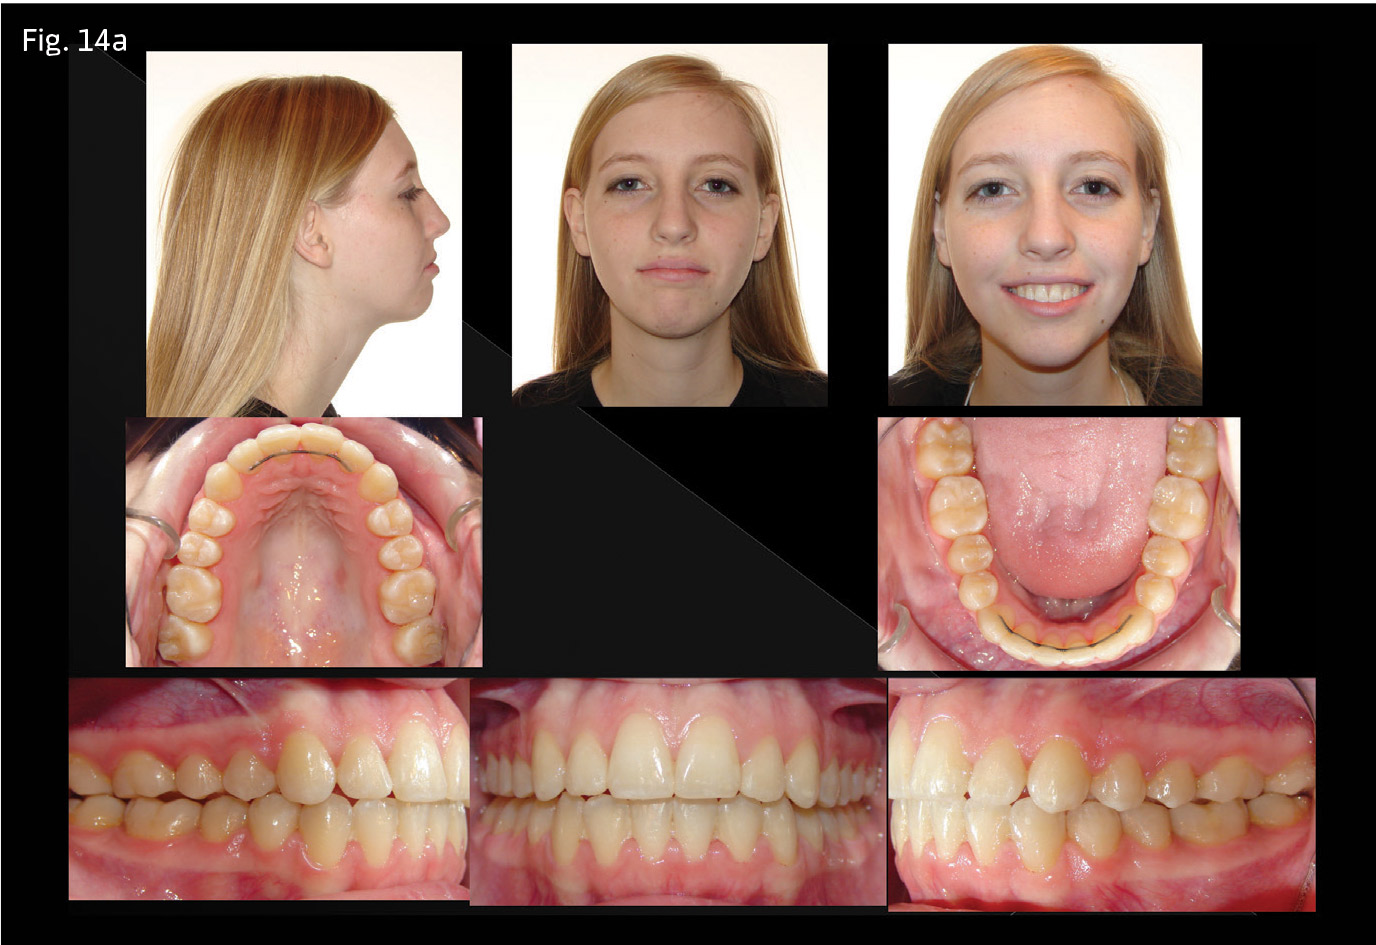

Upon bite closure in both cases, 19x25 titanium molybdenum alloy (TMA) wires were inserted, the TPA was removed and standard techniques were used for detailing and finishing (Figs. 14a–c, pg. 30 and 15a–c).

Both cases were of 18-year-old females, and carried similar treatment objectives:

- Achieve ideal occlusal relationships of overbite and overjet, as well as molar and canine relationships.

Anteroposterior: Molar canine relationships are a half-step Class II. The overjet measurement is 4mm, measured at the left central incisor. The skeletal relationships are mildly Class II. The mandible is posterior divergent, and the lower anterior face height is larger than average.

Vertical: An anterior open bite of 5mm is measured at the right maxillary lateral incisor. The maxilla shows posterior vertical maxillary excess—upon smiling, there is 5mm of gingival display.

Perimeter: Moderate crowding is present in both arches.

Transverse: A constricted maxillary arch form relative to the lower arch is present, resulting in buccal-cusp-to-buccal-cusp relationships extending from the second molars to the first bicuspids on both sides, a bilateral posterior crossbite tendency. However, the patient does have adequate lip competence at rest.